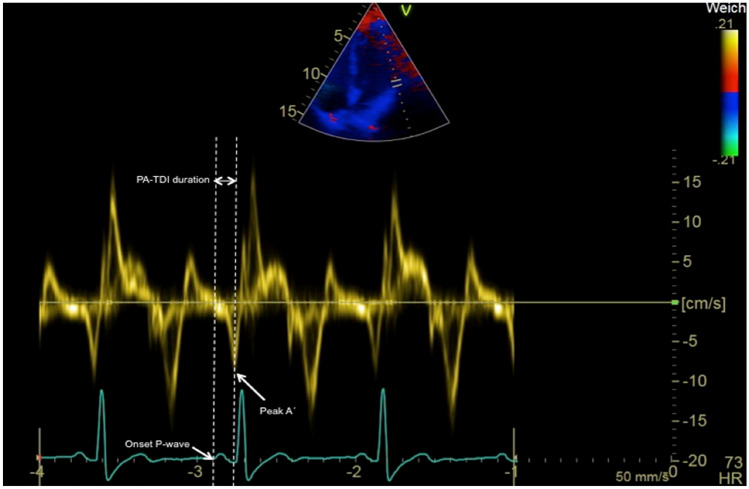

The PA-TDI duration is measured from ECG-gated pulse-wave TDI recordings of the apical four-chamber view using two-dimensional transthoracic echocardiography. Settings are optimized for the highest framerate as possible (at least > 115 frames/s, corresponding to a temporal resolution of 8.7 ms or smaller). A region of interest marker is placed at the LA lateral wall just above the mitral annulus providing the tracing of the mechanical activation in that area (Fig. 2). The PA-TDI duration is measured during sinus rhythm as the time interval from the onset of the P-wave in lead II of the surface ECG (start of electrical depolarization) to the peak A’-wave on the tissue Doppler tracing of the LA lateral wall (active atrial contraction).

Fig. 2.

Measurement of the PA-TDI duration. An example of the measurement of total atrial conduction time via PA-TDI duration with 131.3 ms: as time interval from the onset of P-wave in lead II of the ECG to the peak A′-wave of the left lateral atrial wall